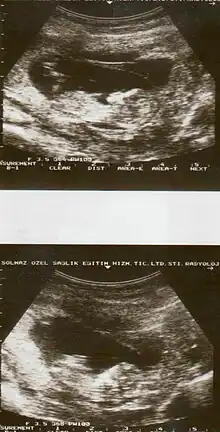

| Diagnostic method | Based on symptoms, ultrasound[1] |

Placental abruption is suspected when a pregnant mother has sudden localized abdominal pain with or without bleeding. The fundus may be monitored because a rising fundus can indicate bleeding. An ultrasound may be used to rule out placenta praevia but is not diagnostic for abruption. The diagnosis is one of exclusion, meaning other possible sources of vaginal bleeding or abdominal pain have to be ruled out in order to diagnose placental abruption.[5] Of note, use of magnetic resonance imaging has been found to be highly sensitive in depicting placental abruption, and may be considered if no ultrasound evidence of placental abruption is present, especially if the diagnosis of placental abruption would change management.[14]